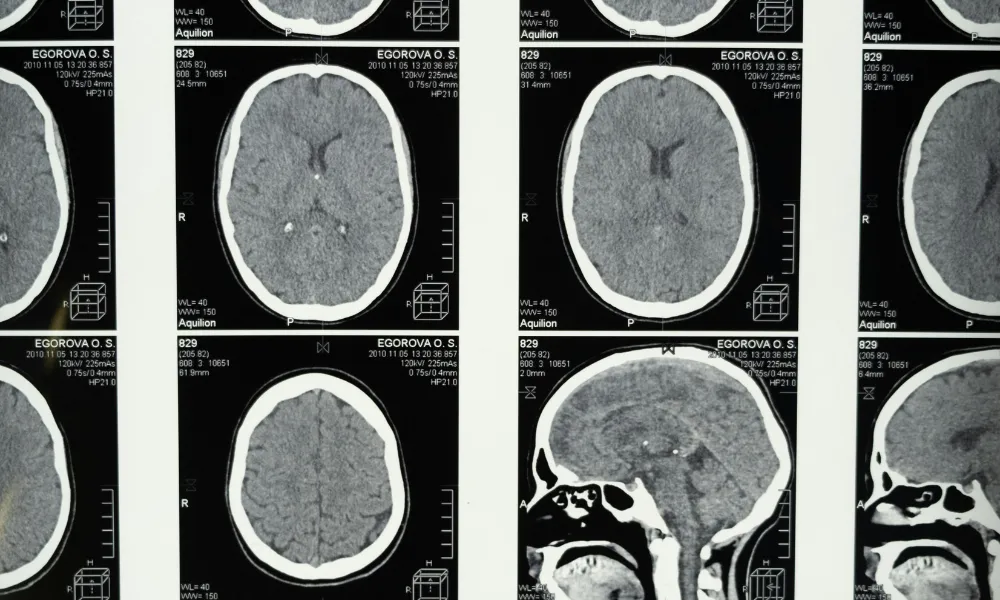

Header Image

Photo Credit: cottonbro studio / pixels.com